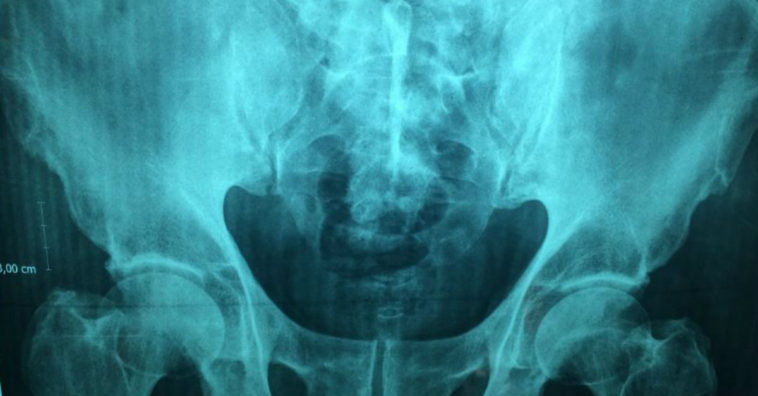

A osteoporose é uma doença caracterizada pela perda da massa óssea devido à redução da quantidade de minerais neles presentes. Essa condição facilita a possibilidade de fratura óssea e afeta três vezes mais mulheres do que os homens. Estima-se que os locais mais afetados pela doença, e que correm mais risco de fraturas, são as vértebras, a bacia, os braços, os pulsos e o fêmur.

Muitas vezes o paciente não percebe que tem osteoporose e o percebe quando começa a desenvolver fraturas nos ossos, principalmente na coluna, quadril, fêmur e os ossos que sofrem impactos com mais frequência.